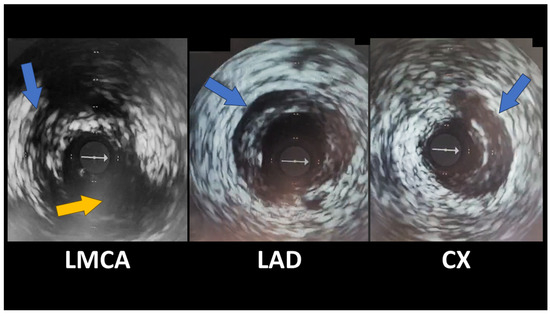

Spontaneous Coronary Artery Dissection Involving the Left Main with Extension to Left Anterior Descending Artery and Left Circumflex Artery: Diagnostic and Management Challenges